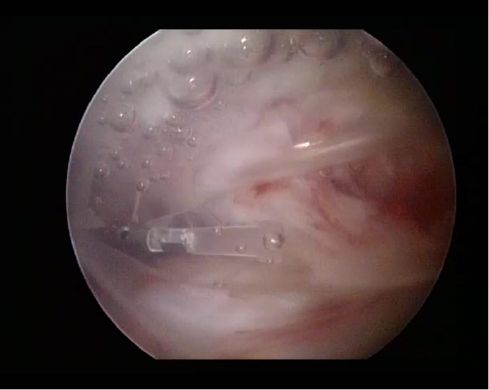

Based on this observation, the following question was raised: Could something be found that will influence the force couples in the coronal plane and counteracts the imbalanced force couples. This was the field where the idea of subacromial spacer was raised. But this was only the beginning. The journey begins in the laboratory, not in the operating room. The material had been selected and tested to be safe. Biodegradable copolymer poly-L-lactide-co-ε-caprolactone (PLCL) was appropriate because it was already used in large number of medical applications, including scaffolds for tissue engineering and drug-loaded films (6,7). PLCL is a flexible but durable material, which mirrors properties of both comprising monomers: the lactide provides the toughness and the caprolactone provides elasticity (8). The unique cold molding technology enabled manufacturing in the shape of balloon, suitable to be implanted between the acromion and the humeral head as it was the first idea (Figure 1). The very first biomechanical experiments were promising, showing the possibility that spacer implantation in the subacromial space could help to restore the force balance between the deltoid muscle and rotator cuff, to maintain humeral head in the stable position during dynamic movement and to decrease sub-acromial friction.